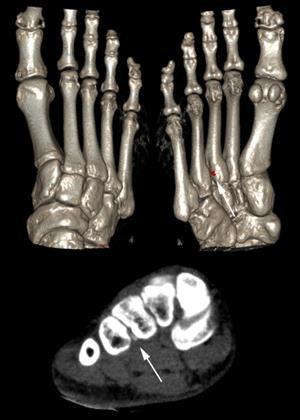

The researchers found 21 cases of gout. Osteoarthritis was evident in 15 joints using CT and 30 joints using DR. There were 134 erosions detected by CT compared with 38 erosions detected by DR. In total, 119 tophi were detected by single-source dual-energy CT compared with 85 tophi by CT and 25 tophi by DR. Single-source dual-energy CT had the best diagnostic value for diagnosis of gout compared with DR and conventional CT.

"Our results suggest that single-source dual-energy CT is able to detect uric acid depositions with good sensitivity and high specificity, including very small lesions (< 1-mm diameters), providing additional diagnostic information compared with DR and conventional CT," the study auhors wrote. "Given the specificity and sensitivity demonstrated here, we suggest single-source dual-energy CT as a problem-solving diagnostic tool in difficult cases with suspected gout, particularly when no joint aspiration can be performed."